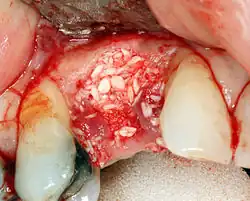

An incision is made across the area and the flap of gingiva is opened to show the bone of the jaw.

An incision is made across the gingiva, and the flap of tissue is reflected to show the bone of the jaw.

If bone width is inadequate it can be regrown using either artificial or cadaveric bone pieces to act as a scaffold for natural bone to grow around.

For an implant to osseointegrate, it needs to be surrounded by a healthy quantity of bone. In order for it to survive long-term, it needs to have a thick healthy soft tissue (gingiva) envelope around it. It is common for either the bone or soft tissue to be so deficient that the surgeon needs to reconstruct it either before or during implant placement.[50]:1084 All techniques of augmenting the alveolar bone in preparation for implant placement are invasive and associated with a degree of morbidity.[59]

To achieve an adequate width and height of bone, various bone grafting techniques have been developed. The most frequently used is called guided bone graft augmentation where a defect is filled with either natural (harvested or autograft) bone or allograft (donor bone or synthetic bone substitute), covered with a semi-permeable membrane and allowed to heal. During the healing phase, natural bone replaces the graft, forming a new bony base for the implant.[56]:223